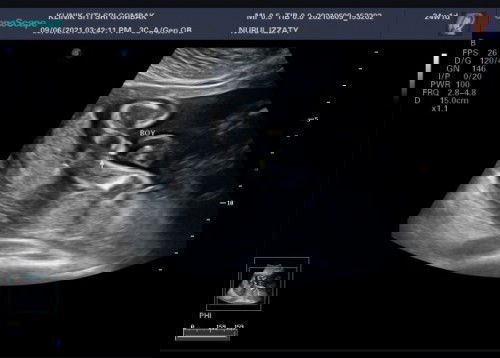

Confirm ke baby boy?

Confirm ke ni anak lelaki? Bentuk perut ramai yang cakap perempuan. ๐Ÿ˜‚ Alhamdulillah settle detail scan, baby dalam keadaan sihat. 24w 1d #ingintahu

kalau mcm ni mcm boy.. sbb npak telur dia.. bentuk perut saya boy je girl ke sama je sis, still tajam ke depan & pusat still terkeluar ๐Ÿ˜